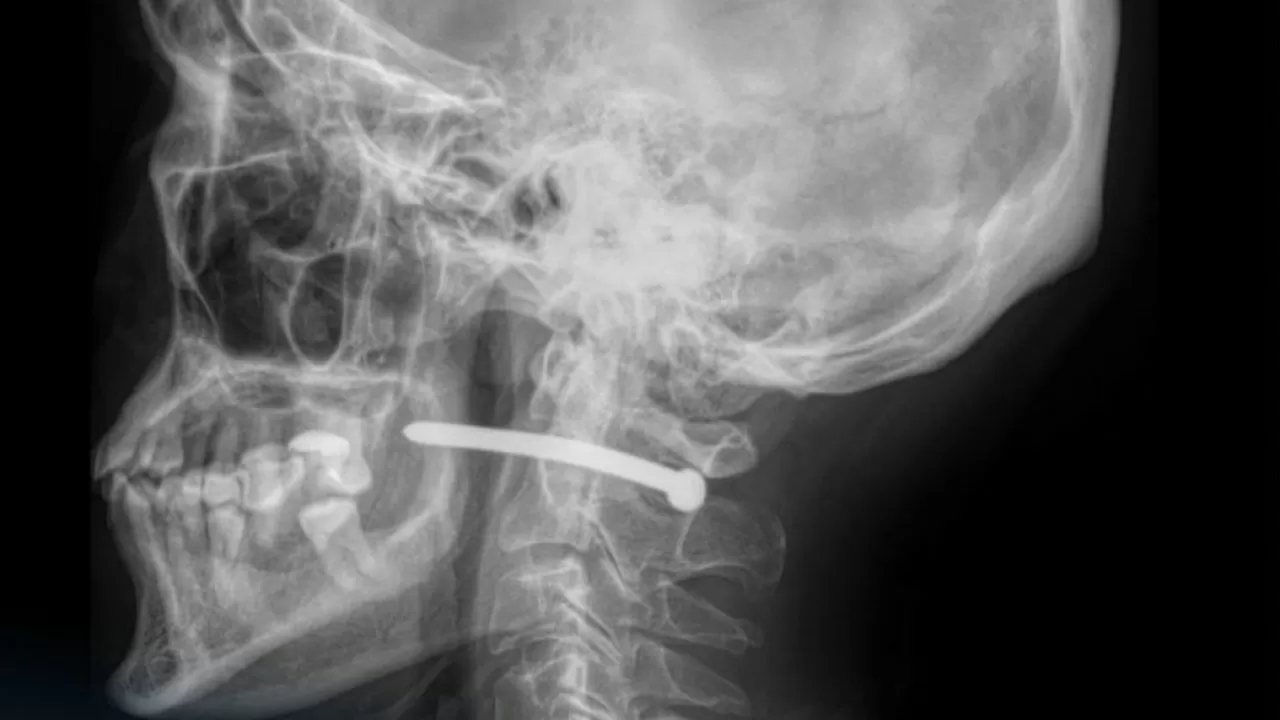

Петропавл қалалық көпбейінді ауруханасы рентгендік зерттеуден кейін мынадай қорытынды шығарған. Пневматикалық пистолетпен атылған шеге ер адамның құлағы маңына кіріп, мойын омыртқасы жанын тесіп өткен.

Ақ халаттылардың сөзінше, маңызды мүшелердің зақымдануына сәл ғана қалған.

Қазіргі уақытта жақ-бет хирургтері шегені алып, тиісті ем-дом жасаған. Кейін жараны тігіп, науқасты бірқатар ұсыныммен үйге шығарған.